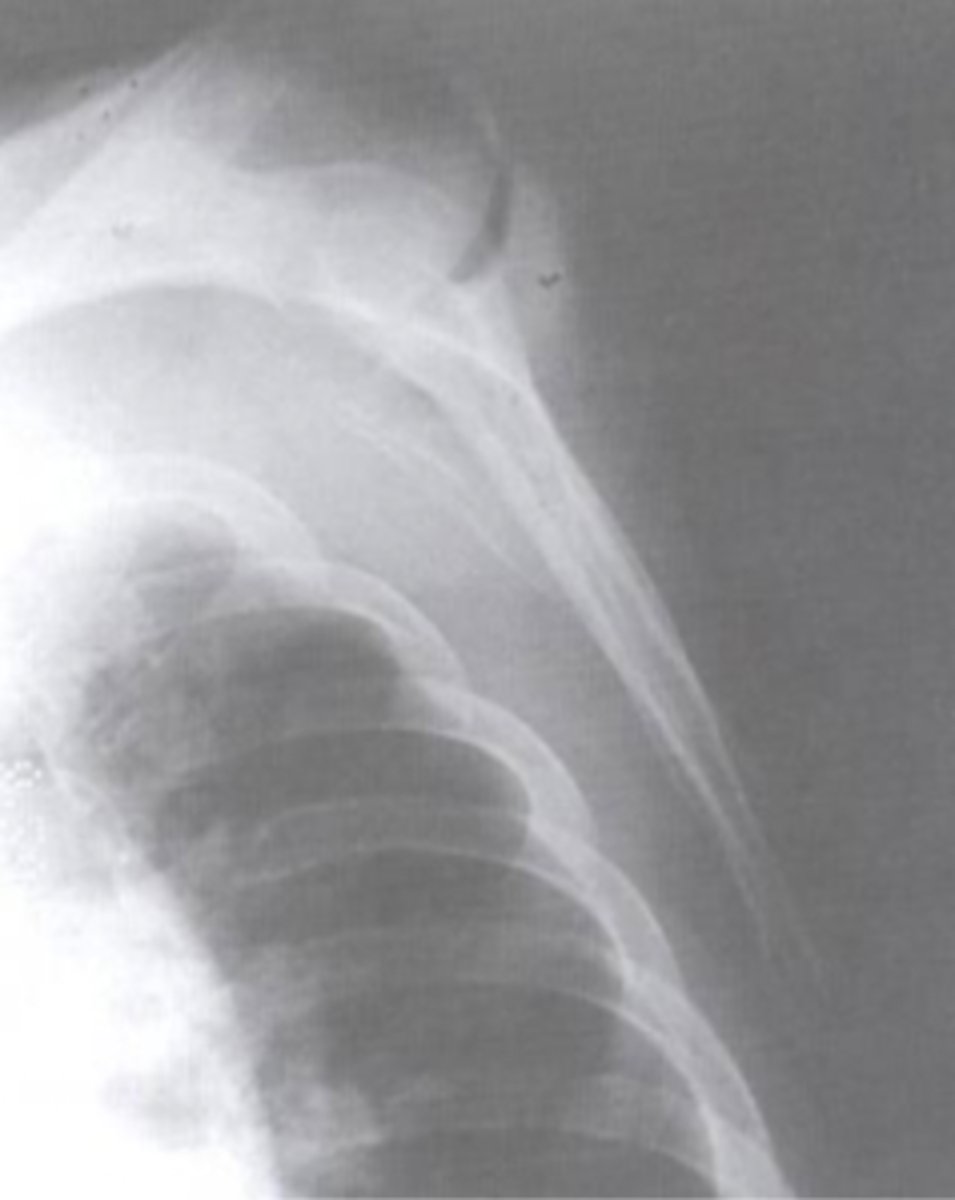

AP scapula

What view is this?